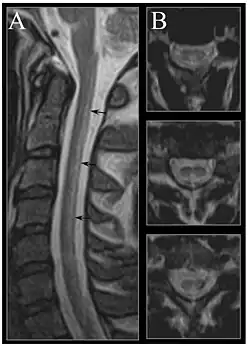

Image of the cervical spinal cord in vitamin B12 deficiency showing subacute combined degeneration. (A) The midsagittal T2-weighted image shows linear hyperintensity in the posterior portion of the cervical tract of the spinal cord (black arrows). (B) Axial T2-weighted images reveal the selective involvement of the posterior columns.

MRI of the brain may show periventricular white matter abnormalities. MRI of the spinal cord may show linear hyperintensity in the posterior portion of the cervical tract of the spinal cord, with selective involvement of the posterior columns.